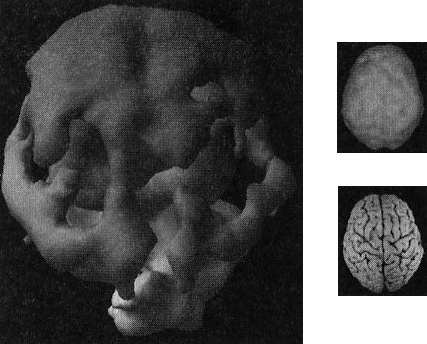

Давайте взглянем на несколько примеров здорового и не очень здорового мозга. Однажды я предложил студентам стать добровольцами в исследовании функционирования мозга. Кристи, одна из вызвавшихся, воскликнула: «Вам обязательно нужно проверить мою бабушку Анну. Ей 82 года, но среди всех, кого я знаю, она одна из самых нормальных. Она вам понравится!» Бабушка согласилась, и мы провели томографию. Действительно, обнаружилось, что мозг этой пожилой женщины здоров, а ее жизнь соответствует всем критериям профилактики здоровья мозга (она не употребляла наркотики, не получала травм головы, не имела родственников первой степени с психиатрическими заболеваниями и т. д.). В течение 58 лет Анна была замужем, всегда оставаясь любящей женой, матерью и бабушкой, ее ум был острым и деятельным. Кроме того, она активно участвовала в делах местной церкви и муниципалитета. Она создала прочные и длительные отношения с родными и друзьями. Скан мозга Анны — один из самых здоровых в моей базе данных (рис. 2.5 и 2.6).

Скан здорового мозга Анны, 82 года

Рис. 2.5 Вид сверху

Полная симметричная активность

Рис. 2.6 Вид снизу